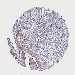

TESTIS CANCER - Protein expressioni

A mouse-over function shows sample information and annotation data. Click on an image to view it in a full screen mode. Samples can be filtered based on level of antibody staining by selecting one or several of the following categories: high, medium, low and not detected. The assay and annotation is described here.

Note that samples used for immunohistochemistry by the Human Protein Atlas do not correspond to samples in the TCGA dataset.

Antibody stainingi

Antibody staining in the annotated cell types in the current human tissue is reported as not detected, low, medium, or high, based on conventional immunohistochemistry profiling in selected tissues. This score is based on the combination of the staining intensity and fraction of stained cells.

Each image is clickable and will lead to virtual microscopy that enables deeper exploration of all samples and also displays staining intensity scores, fraction scores and subcellular localization as well as patient and tissue information for each sample.

Antibody HPA043075

Staining

High

Medium

Low

Not detected

Intensity

Strong

Moderate

Weak

Negative

Quantity

>75%

75%-25%

<25%

None

Location

Nuclear

Cytoplasmic/membranous

Cytoplasmic/membranous,nuclear

Carcinoma, Embryonal, NOS

Seminoma, NOS